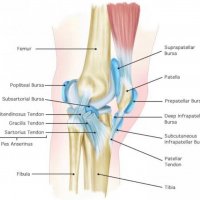

Knee bursae are sacs surrounding the knee joint that are filled with synovial fluid.

They facilitate movement and reduce friction where tendons or muscles pass over bony prominences.

The knee bursae can be either communicating or non-communicating with the knee joint itself.

There are four bursae anterior to the knee joint, each two bursae at medial and lateral knee, and also four bursae posterior to the knee joint.